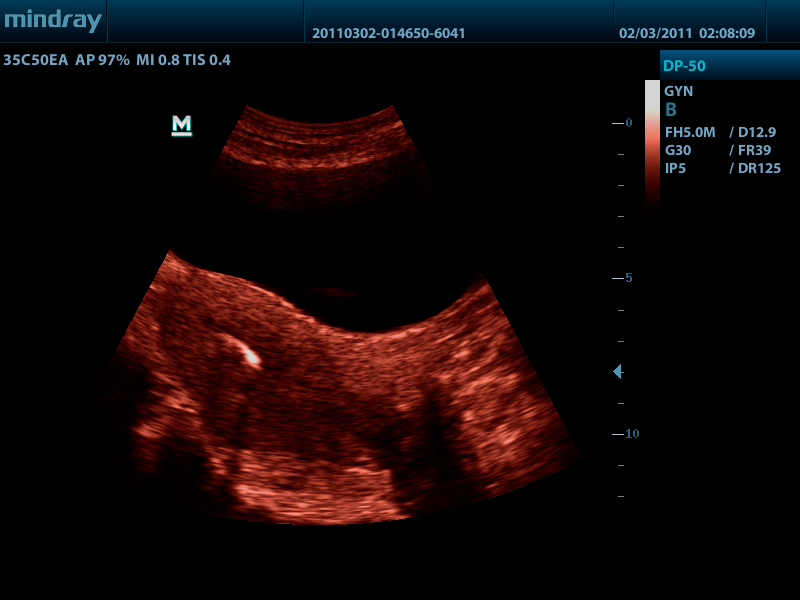

Конвексный датчик 35C50EA (2.0/3.5/4.5/5.0/Н5.0/Н6.0) R50

Микроконвексный датчик 65C15EA (5.0/6.5/7.5/8.5/Н8.0/Н9.0 МГц, R-15 )